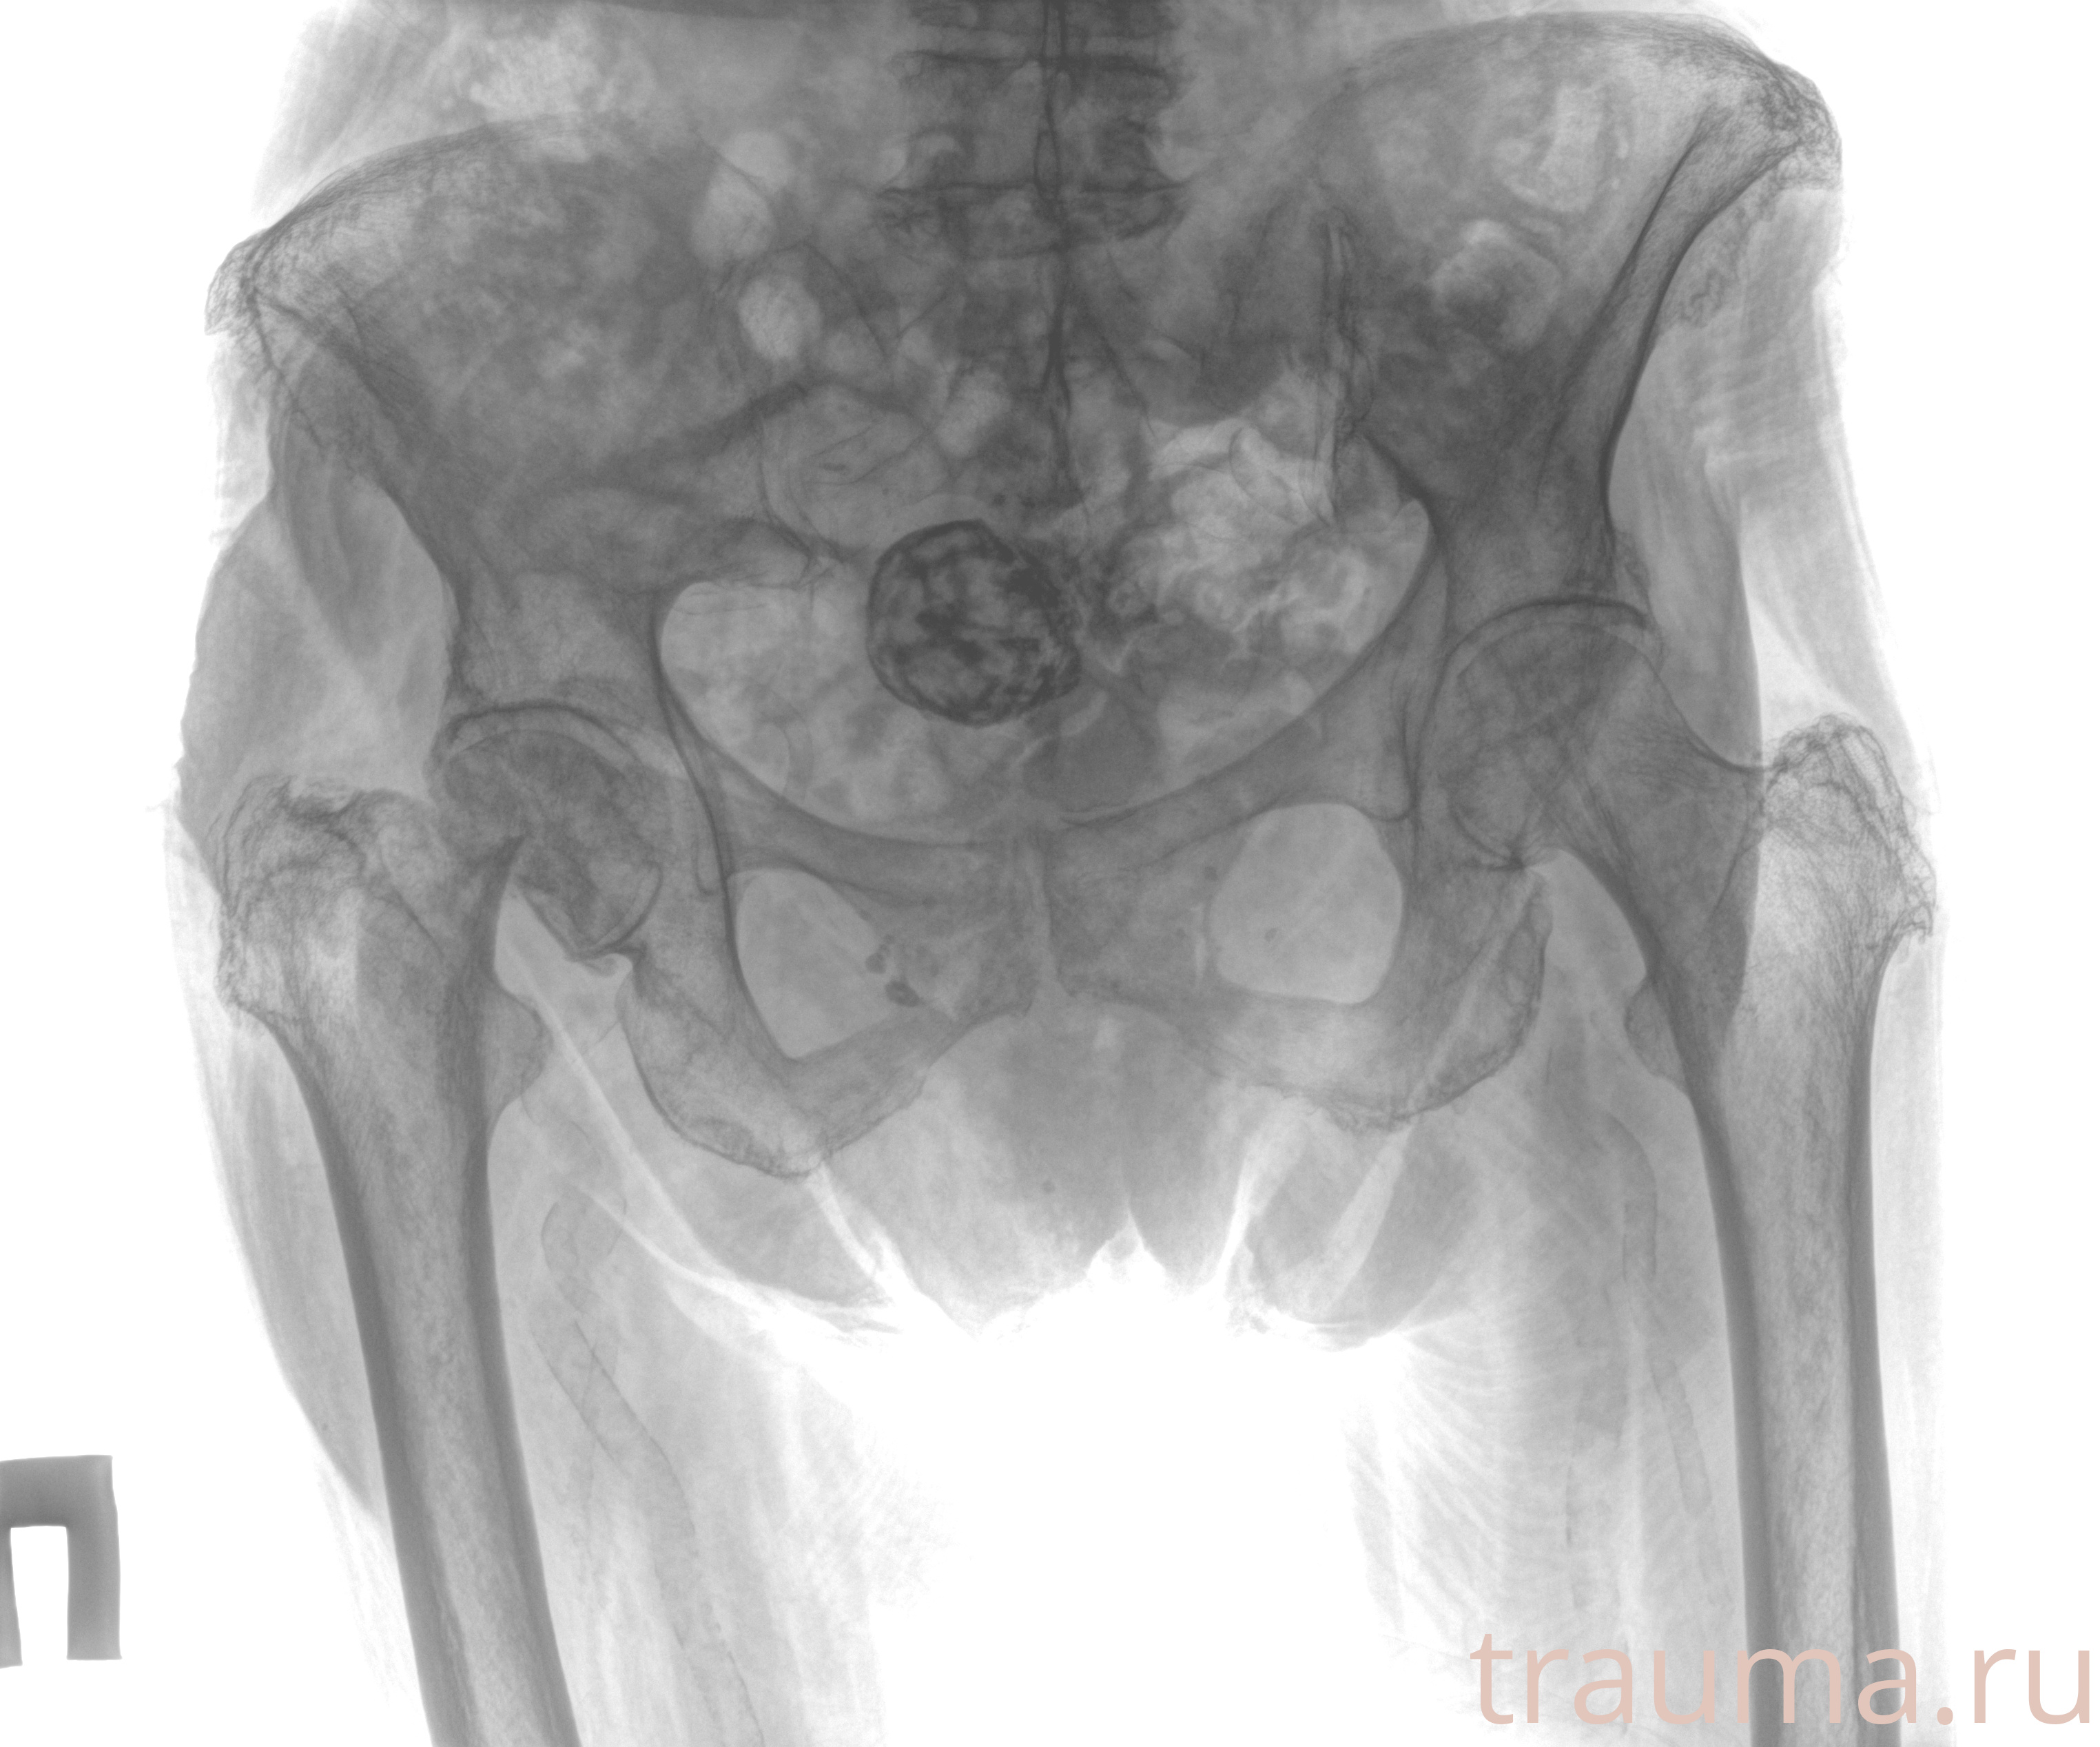

Рентгенограммы

Рентген на дому: по вашему адресу приезжает врач-рентгенолог, травматолог-ортопед с мобильным рентгеновским аппаратом, проводит диагностику травмы или заболевания, делает необходимые рентгенограммы, дает рекомендации по дальнейшему лечению. Получить качественные снимки в домашних условиях возможно благодаря уникальной методике, разработанной МосРентген Центром для института  Склифосовского